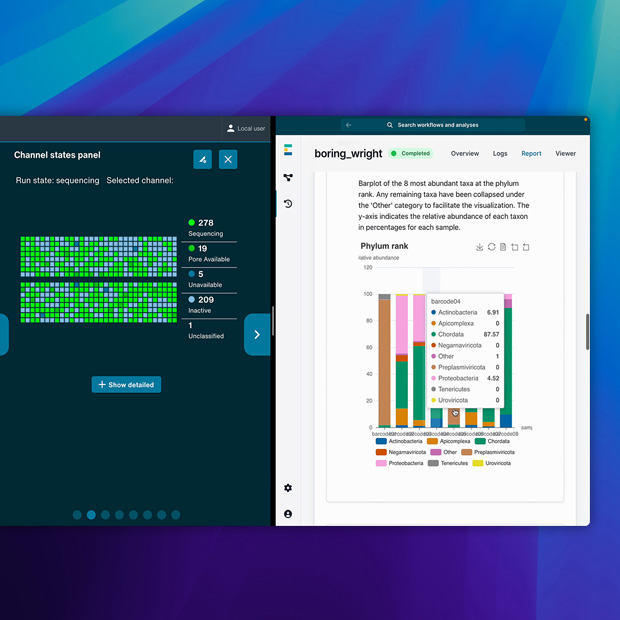

Visage 7 讓醫生能在 iPad、iPhone 和 MacBook Pro 上超高速存取 DICOM 影像,以便進行高效的診斷分析。Visage Ease 支援 iPad 及 iPhone。